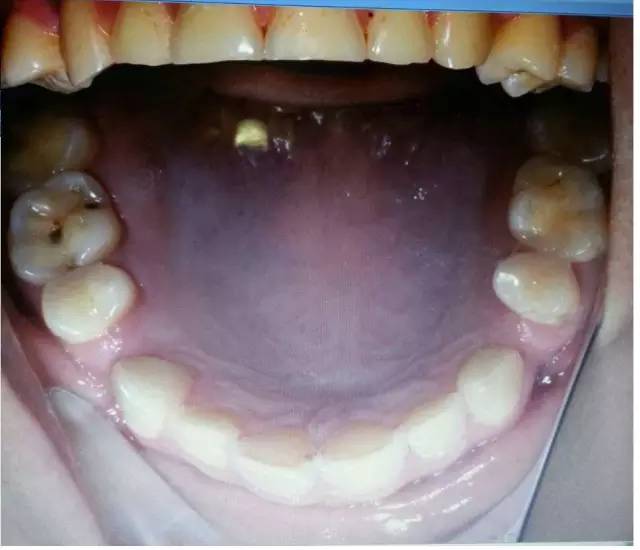

您可能已經(jīng)關(guān)注到患者全口牙磨耗較明顯,請試著思考“牙齒出現(xiàn)缺損有哪些因素?”

磨耗是超過生理范圍的牙體磨損,是一種病理性磨損,臨床上磨損可并發(fā)各種病癥或為致病因素,如引起牙本質(zhì)過敏、食物嵌塞牙髓炎、顳頜關(guān)節(jié)病,以及口內(nèi)軟組織創(chuàng)傷性潰瘍,并可成為致癌的因素。

過大的(牙合)力通常是造成磨耗的原因,還有醫(yī)生指出,如患嬰兒式吞咽方式,舌頭在吞咽時會對牙齒產(chǎn)生推力,導(dǎo)致應(yīng)力集中的頸部出現(xiàn)微折裂也是原因之一。以上幾點都是造成牙體缺損的機(jī)械因素哦!其實這個病例給了我們很多信息,需要我們細(xì)致的檢查和問診,來吧,跟著權(quán)老師探究隱藏在表象之下的真相:牙齒出現(xiàn)缺損除了機(jī)械因素,還有什么因素?

是的,牙齒缺損還可能是化學(xué)因素造成的。權(quán)老師追問患者是否有胃病,追問飲食習(xí)慣,果真發(fā)現(xiàn)諸多玄妙之處。“患者喜歡吃酸東西,每頓飯必吃醋,吃完馬上就刷牙。”沒想到吧,這些看似不起眼的飲食習(xí)慣也能探究出與牙齒磨耗的因果關(guān)系,難怪群里郭耀銘老師忍不住感嘆權(quán)老師分享的病例酸味十足哩!這種酸酸的味道是要讓大家學(xué)會分辨機(jī)械因素和化學(xué)因素導(dǎo)致的牙體缺損。